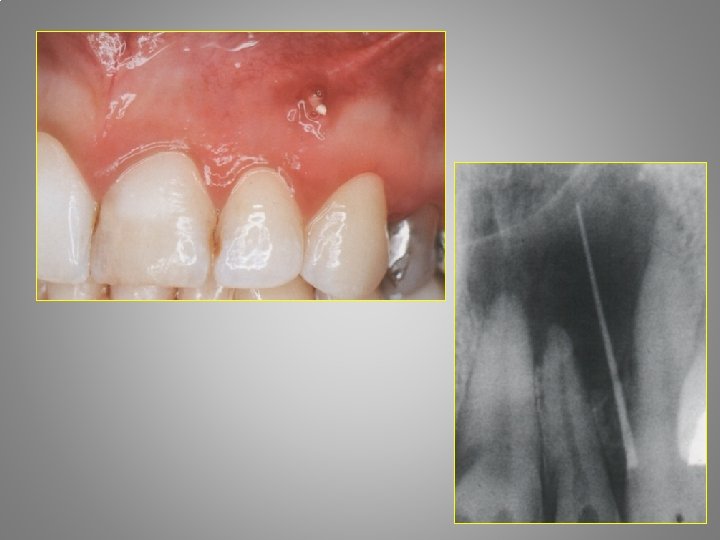

• 37 years old woman. Nothing in the medical history. • Complain started two days before. It stated with pain in the lower left molars and sensitivity to cold. In the first evening a painkiller pill was help. On the second day the pain was stronger a, d she can’t sleep. Today the pain is very strong she can’t eat or touch the first molar tooth with her tongue.